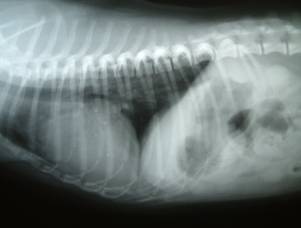

- 門脈大静脈短絡|X線検査にて疑うことができる

-

- 肝臓が縮小時に腎臓が拡大

- 側面像では正常の胃は肋骨に沿うが肝臓の縮小があると胃が頭側変位する背腹像では胃が横隔膜に近づく